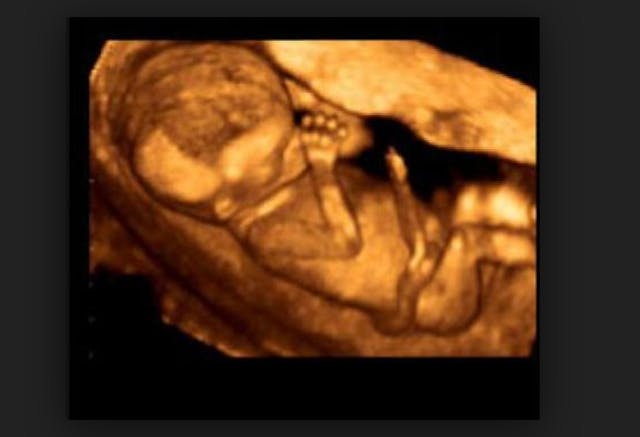

Here is an ultrasound of a ten-week-old preborn child. Note how developed the baby is. This is definitely a child who is “fully formed.” And yet, 92 percent of abortions are performed at 13 weeks or earlier.